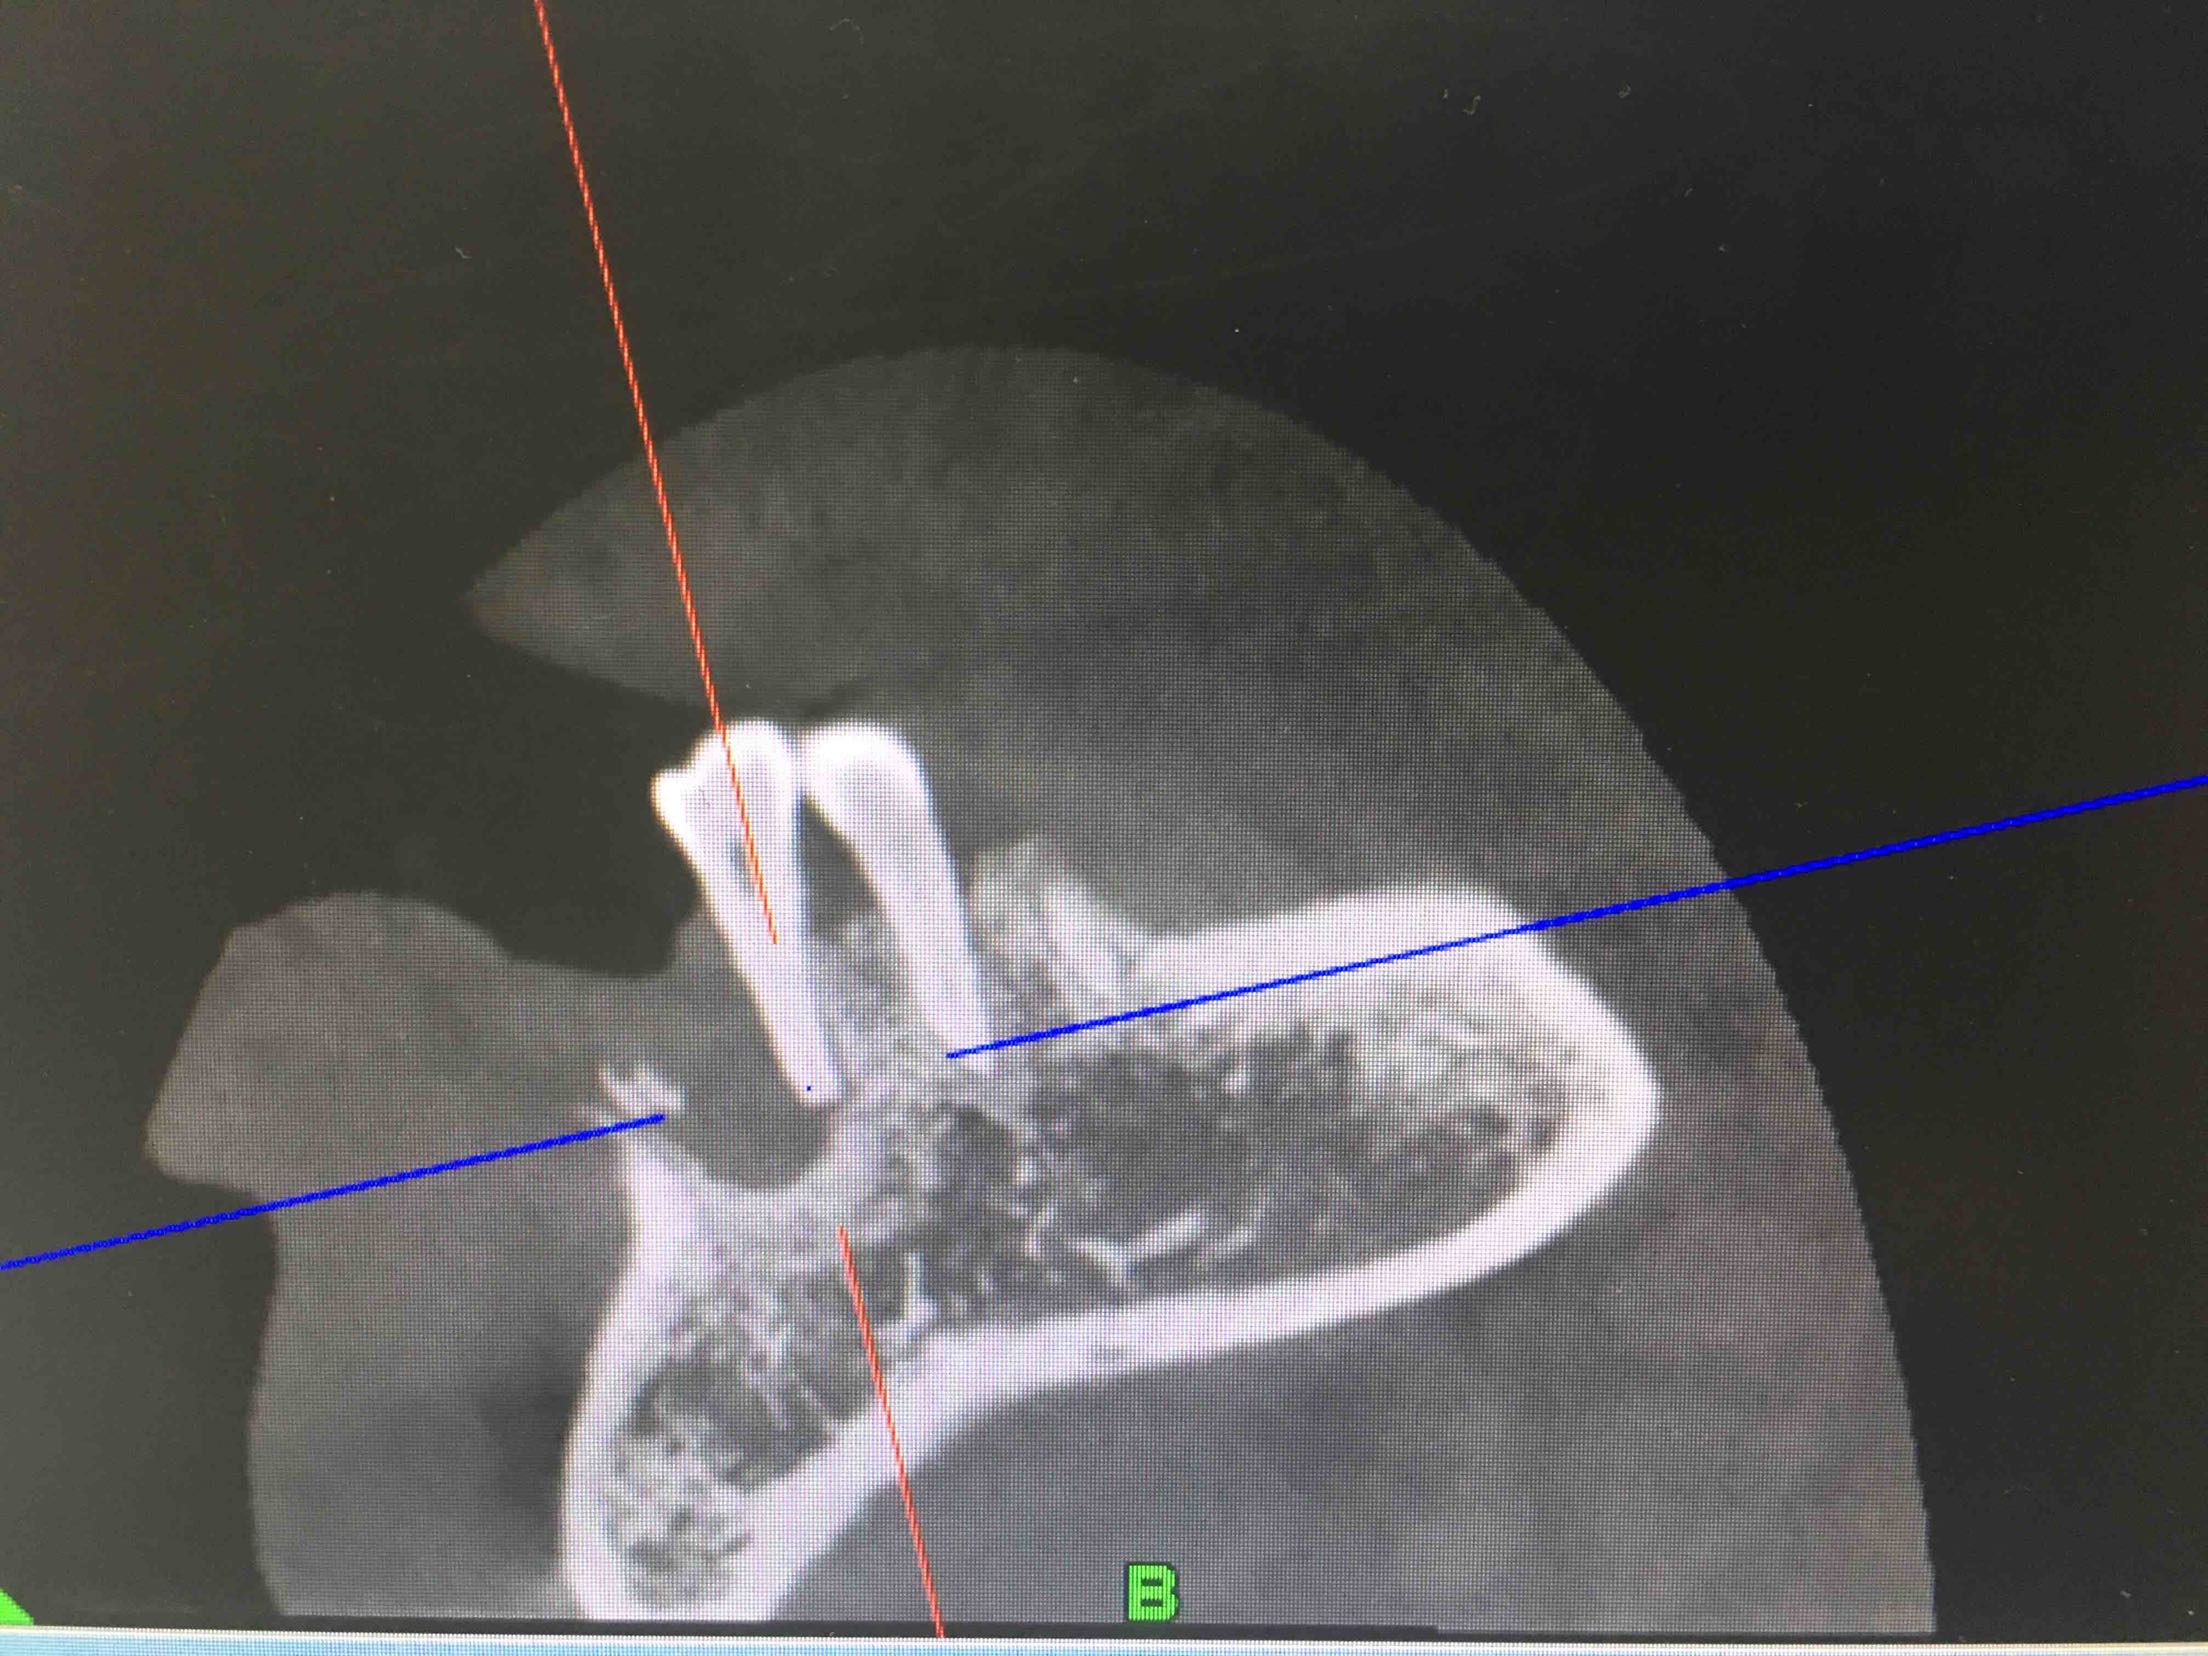

41、43、44牙松动2-3度,42牙缺失,全景片及CBCT显示牙槽骨吸收严重。

两周后,局麻下,翻瓣拔除44牙,在41、42根方环形钻取骨块,钛钉固定于43牙骨缺损处,Bio-ss骨粉0.25g,海奥生物膜,严密缝合!嘱半年后植牙!

植入42、44登腾3.4-10两枚植体